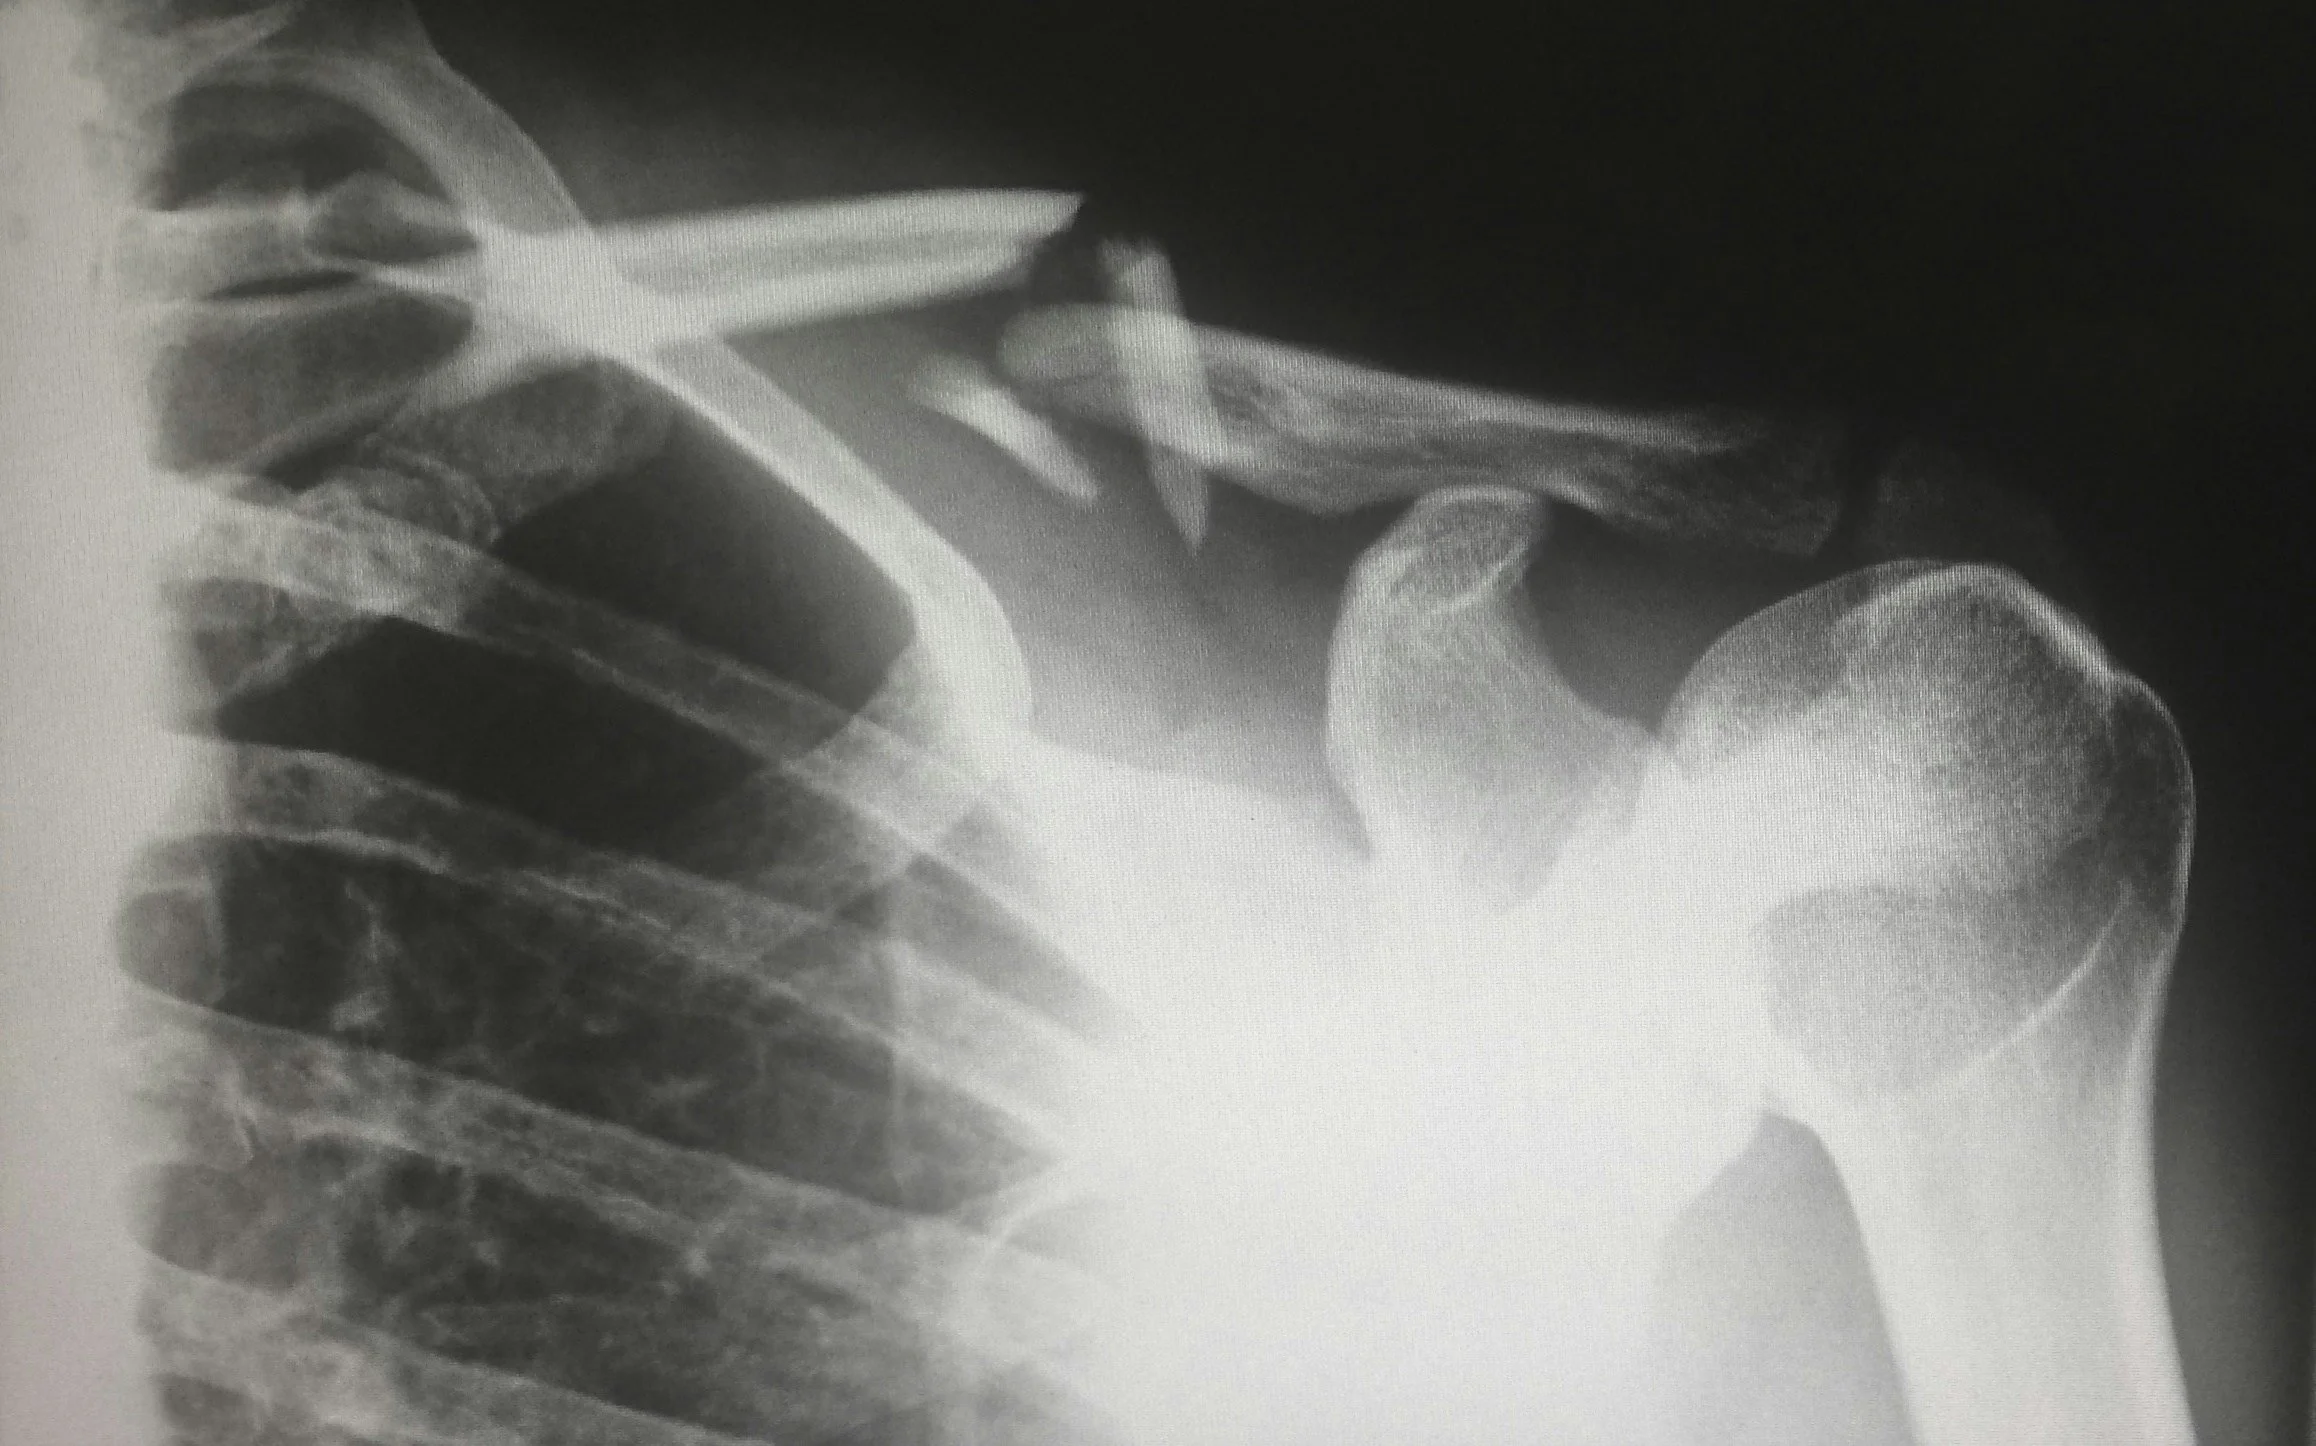

La resonancia magnética de hombro es una técnica de diagnóstico por imagen que permite obtener una visión detallada de la articulación del hombro y los tejidos que lo rodean. Este estudio es esencial para evaluar lesiones en tendones, músculos y tejidos circundantes, así como para el diagnóstico de diferentes padecimientos, la planificación de tratamientos y el monitoreo de enfermedades crónicas del hombro.